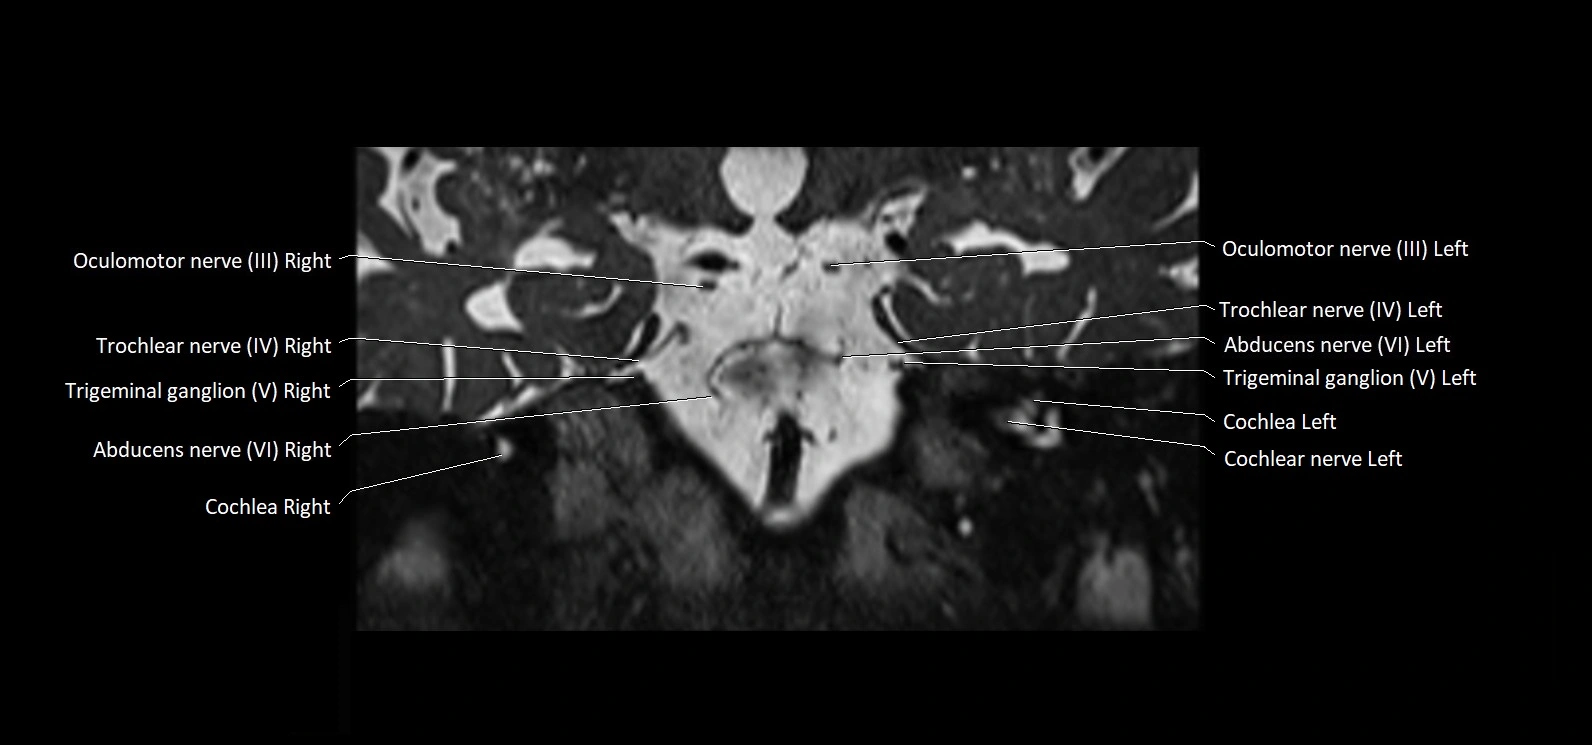

MRI Appearance

• The abducens nerve is a small, thin, linear structure

• Best visualized on high-resolution T2-weighted 3D MRI sequences (e.g., FIESTA or CISS)

• Seen as a hypointense (dark) line running from the brainstem at the pontomedullary junction, traversing the prepontine cistern, and entering Dorello’s canal under the petrosphenoidal ligament, then into the cavernous sinus, and finally the orbit

• May be challenging to visualize in standard MRI due to its small size

• Pathology may be inferred by absence, displacement, or enhancement of the nerve

MRI images

image